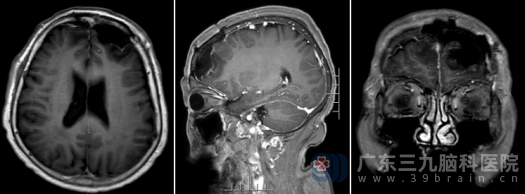

经过周密的术前准备,由科室专家主刀,在全麻下为王阿婆实施了开颅肿瘤切除术。手术历时5个小时,术中可见病变血供异常丰富,与术前影像学判断完全吻合。凭借精湛的显微神经外科手术技巧,医生在充分保护正常脑组织及重要功能区的前提下,将肿瘤完整切除。术后MR复查显示:病变已完全切除。

得知病理结果属于良性(WHO 1级),且手术切除干净,王阿婆的家人悬着的心终于放下。术后王阿婆恢复顺利,出院时神志清醒,四肢活动自如,未留下任何神经功能障碍,生活质量得到了极大改善。